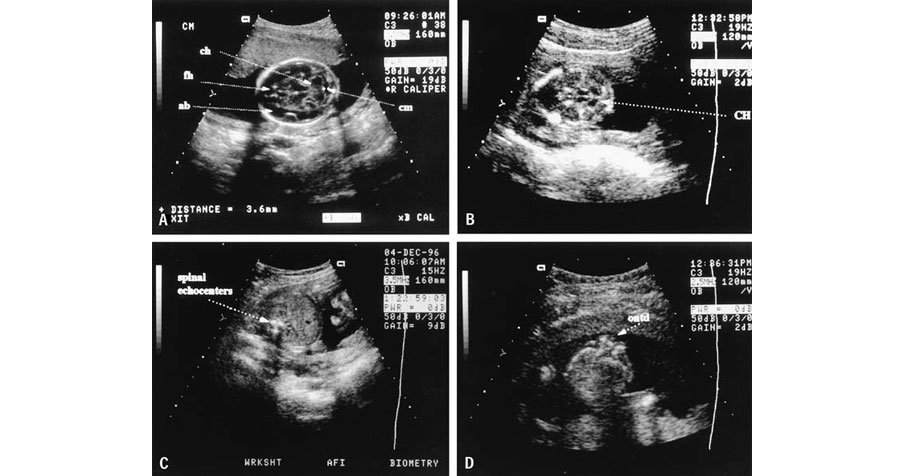

Routine obstetric sonography, commonly known as prenatal ultrasound, is a standard medical imaging procedure performed during pregnancy to monitor the development and health of the fetus. Using high-frequency sound waves, a transducer is placed on the abdomen or inserted into the vagina to create images of the uterus, placenta, and fetus. This imaging technique provides valuable information about the baby's growth, position, and anatomy, helping healthcare providers assess for any potential abnormalities or complications. Routine obstetric sonography plays a crucial role in determining the due date, identifying multiple pregnancies, checking for fetal well-being, and diagnosing conditions such as congenital anomalies or placental issues, contributing to the optimal management and care of both the mother and the unborn child throughout pregnancy.

• NT / NB scan (11-14 weeks)

• Anamoly scan (18-20 weeks)

• fetal echocardiography (18-26 weeks)